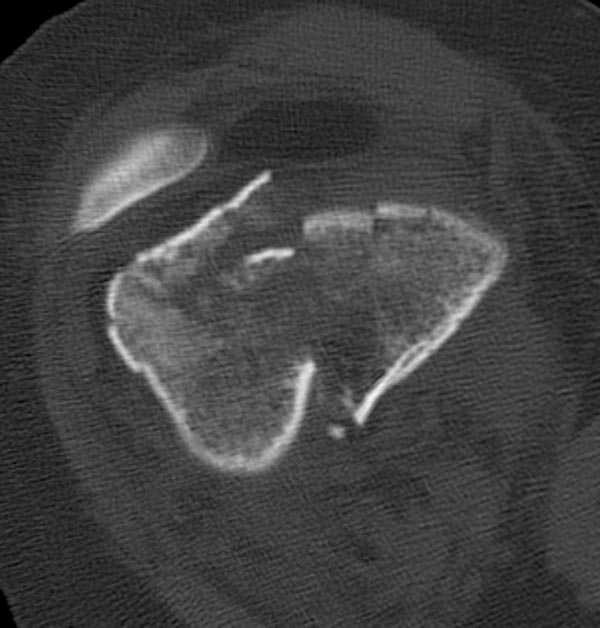

Это перелом не нижней трети, а дистального суставного конца, с распространением на диафиз. Что-то между C2 и C3. Но пока ближе к C2 по увиденному - вторую проекцию еще не показали.

На профиле стало видно, что открываться придется, это перелом C3, хотя можно назвать и C2+, т.е. с еще и фронтальным раскалыванием одного мыщелка. Надо сделать медиальную артротомию, ступеньку на внутреннем мыщелке устранить, ввести либо несколько временных спиц спереди назад, или сразу винт вдоль эллипса мыщелка. А дальше как выше написано - дистрактор, и штифтовать. Учитывая наличие открытого колена - вполне уместно ретроградно.

еще кт